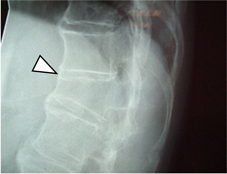

除了改善疼痛外,最重要的是希望能減少脊椎沾黏的併發症,如:嚴重的患者可能脊椎沾黏如竹竿,活動受限且無法正常地彎腰轉頭(如圖二),有些伴隨嚴重的周邊性下肢寡關節炎(如圖三)。

圖二、僵直性脊椎炎病人的側面腰椎X光。有所謂的邊緣骨刺(白色箭頭)